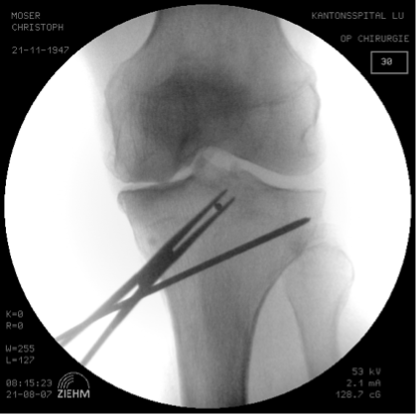

Distraction of the osteotomy (multi-chisel technique) and plastic deformation of the lateral hinge with the distractor

Introduction of a first chisel (20 mm size) below the K-wires. This is advanced under image intensifier control up to around 5 mm before the lateral cortex. The next chisel (20 mm size) is advanced below it, also up to around 5 mm from the cortex. Thereafter, a further chisel (25 mm size) is carefully advanced between these two chisels up to around 15 mm from the lateral cortex. The chisels should be introduced slowly (Fig. 7a).

This creates a plastic deformation of the hinge with controlled microfractures that taper parallel to the first two chisels. With larger corrections another 2−4 chisels can be introduced; each one is introduced a little less far than the previous ones. Thereafter we remove the two K-wires and the chisels. At this time in the operation the lateral hinge should still be sufficiently stable under image intensifier control and should not be shifted. However, if the osteotomy tools are advanced too far it can result in uncontrolled fractures of the hinge and even opening up or shifting of the osteotomy at the lateral hinge.

As the next step, an arthrodesis distractor is fully inserted dorsally and slowly distracted. We close and open the distractor carefully several times. This gives an indication of the elasticity of the osteotomy. If there is still a lot of resistance it can be either due to an insufficient release of the superficial medial collateral ligament or to an incomplete dorsolateral osteotomy. With an incomplete osteotomy the dorsolateral cortex can be further weakened with a rounded chisel under image intensifier control. The hinge should have good mobility but must be preserved.

Control of the correction in the frontal and sagittal plane

Now we position the knee in extension, support the heel with a roll. The knee should be fully extended. This is particularly important in knees with a preoperative extension deficit. Any extension deficit hast to be corrected during the operation. This is achieved by a reduction of the tibial slope by pushing the knee down in full extension by the assistant. We control the change of the tibial slope with the two anterior K-wires (Fig. 7b).

Due to the triangular form of the tibia the biplanar osteotomy is always opened about 30% more dorsally than anteriorly [25]. Now we measure the size of the correction on the central tibia edge and compare it against our plan (Fig. 7c).

Then the intraoperative Mikulicz line in full extension of the knee is documented under image intensifier control. The anterior K wires introduced at the start of the operation accurately show us any changes to the rotation and the slope (Fig. 7d). The use of computer-assisted navigation is helpful in complex two-dimensional corrections (Fig. 7e).